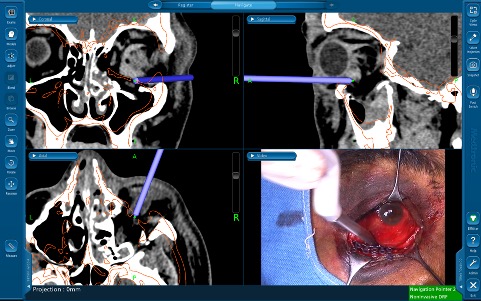

Image-guided surgical navigation (ISN) is a useful tool in orbital surgery which allows for 3-dimensial (3D) localization of the surgeon’s instruments within a confined space which holds important vascular and neural structures. It has long been used in surgical specialties beyond oculofacial plastic surgery. First employed by neurosurgeons to aid in tumor localization, the use of ISN has since expanded to otolaryngology, dental, spinal and now more recently orbital surgery.[1] Intraoperative navigation relies on the principle of stereotaxy, whereby external markers are used as a reference point, allowing for three planes of visualization to localize internal surgical/anatomical landmarks. Stereotactic surgery enables the surgeon to precisely direct surgical instruments or radiation towards a specific area thereby improving surgical precision, instrumentation and reducing intra-operative complication rates.[2]

Image-guided surgical navigation has been used in orbital surgery to aid in pre-operative planning, allowing the surgeon to determine the most minimally invasive route that would yield the least collateral damage to surrounding tissue. Navigation assistance also enables the surgeon to account for any possible anatomical variations or incidental findings that may complicate the surgery.

- Imaging data set: Pre-operative imaging in the form of contiguous CT/MRI imaging series are required to allow for accurate calibration of image-guidance equipment. The set of images is then uploaded to the navigation software to create a 3D map of the patient’s anatomy.

- Localizers: This comprises of an emitter (infrared or electromagnetic) and a patient tracker (usually a headband) that communicate with one another to convert the position of the sensors into relative coordinates. Positioning of all components is essential to allow for free signal transfer between.

- Surgical instrument or probe: The signal emitted localizes the probe on the 3D map relative to the tracker. Conceptually, ISN is analogous to global positioning systems used in vehicles, with the imaging data set representing the “map”, the localizers (emitter and tracker), representing the satellite and tower, and the probe representing the “car”.